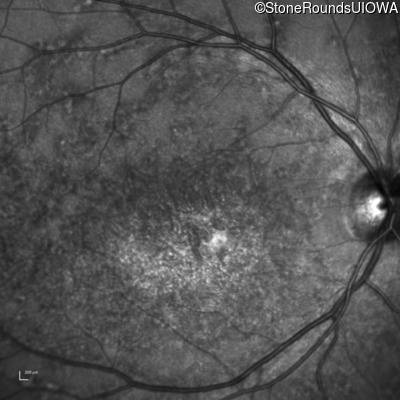

Infrared Fundus Photograph - Left - 20/200

Exemplar